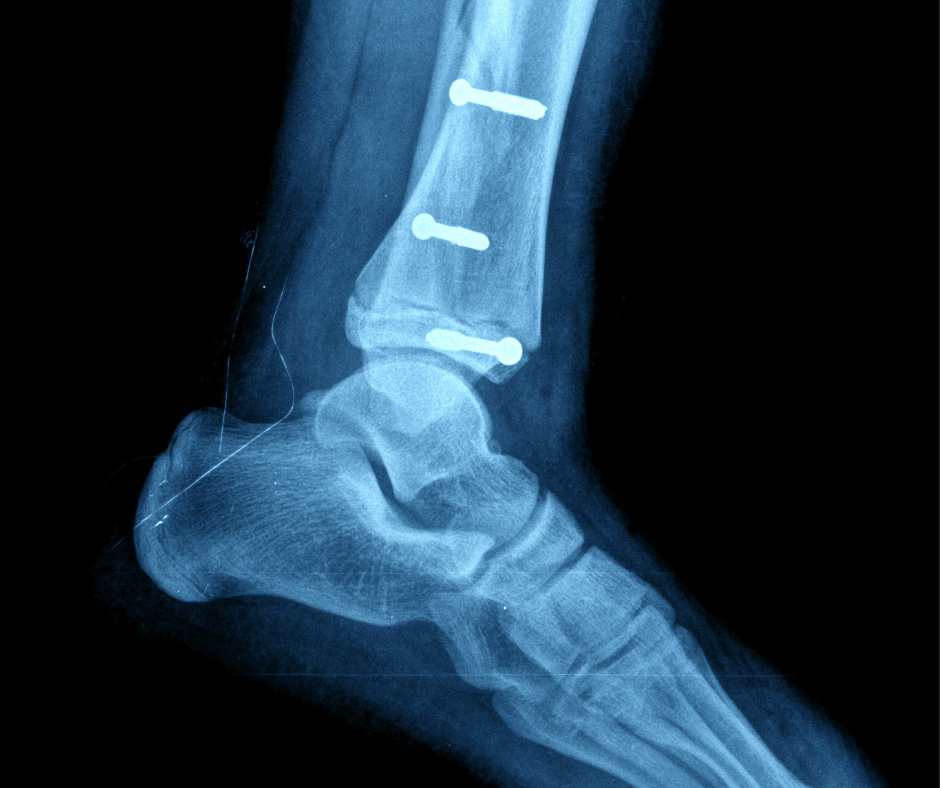

Surgical Screws: Supporting Healing and Ensuring Stability

When people hear about the use of surgical screws, their first reactions tend to stem from what they’ve seen in horror movies, not what they’ve read in medical journals. Yet despite some unfortunate negativity centered on their use in surgical procedures, screws have a very important and therapeutic role in foot and ankle surgery, helping to mend serious injuries and restore full function when other methods might not be able to do so.

- Stabilizing Fractures: During surgery to correct foot fractures, screws are meticulously inserted into broken bones to hold them firmly in place.

- This stability is key for proper healing, preventing displacement of the fragments throughout the process.

- Screws act as an internal support system, promoting optimal recovery for damaged bones.

- Securing Implants: Screws play a vital role in securing implants like plates, rods, and artificial joints to bones in foot surgery.

- They create a stable connection between the implant and the bone, thanks to their structural rigidity.

- This helps prevent implant movement and promotes optimal recovery.